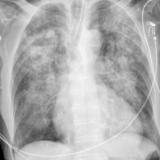

Heart failure

Album: Heart failure

Date: 11/05/2005

Size: 24 items

Views: 57365